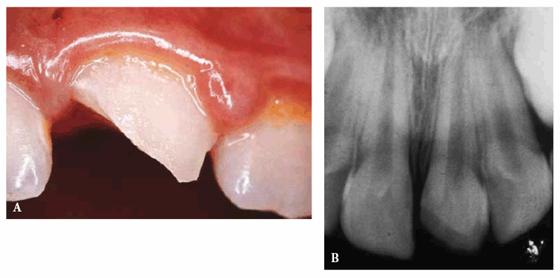

A female patient, 9 years, 2 months old.

PROBLEM: This patient presented with an extended, noncomplicated enamel

and dentin fracture of teeth #8 and #9. Four days had passed since the trauma

occurred, and the fragments had not been hydrated (Figures 27-6A

and B

Figure 27-6A and B: An extended but not complicated enamel and dentin fracture of teeth #8 and #9.

TREATMENT: After performing routine clinical, instrumental, and

radiographic examinations, it was decided to try to rehydrate the tooth

fragments by putting them in a physiologic saline solution for 1 day. In the

meantime, the fit of the tooth fragments was confirmed (Figures 27-6C

and D). The

following day, the two rehydrated tooth fragments had reached their normal

color, and the reattachment of the two fragments proceeded as described above.

Figure 27-6C and D: The tooth fragments have not been hydrated for 4 days. They fit perfectly but are discolored.

RESULT: The result obtained was much better functionally and

esthetically than it would have been using only composite resin. This

one-appointment procedure (due to a perfect fitting of the fragments) has restored

the anterior guide and has reached a correct reproduction of the biting edge (Figures 27-6E

and F

Figure 27-6E and F: The fragments have been rehydrated for 1 day and then reattached. The final result and the patient's smile are satisfying.